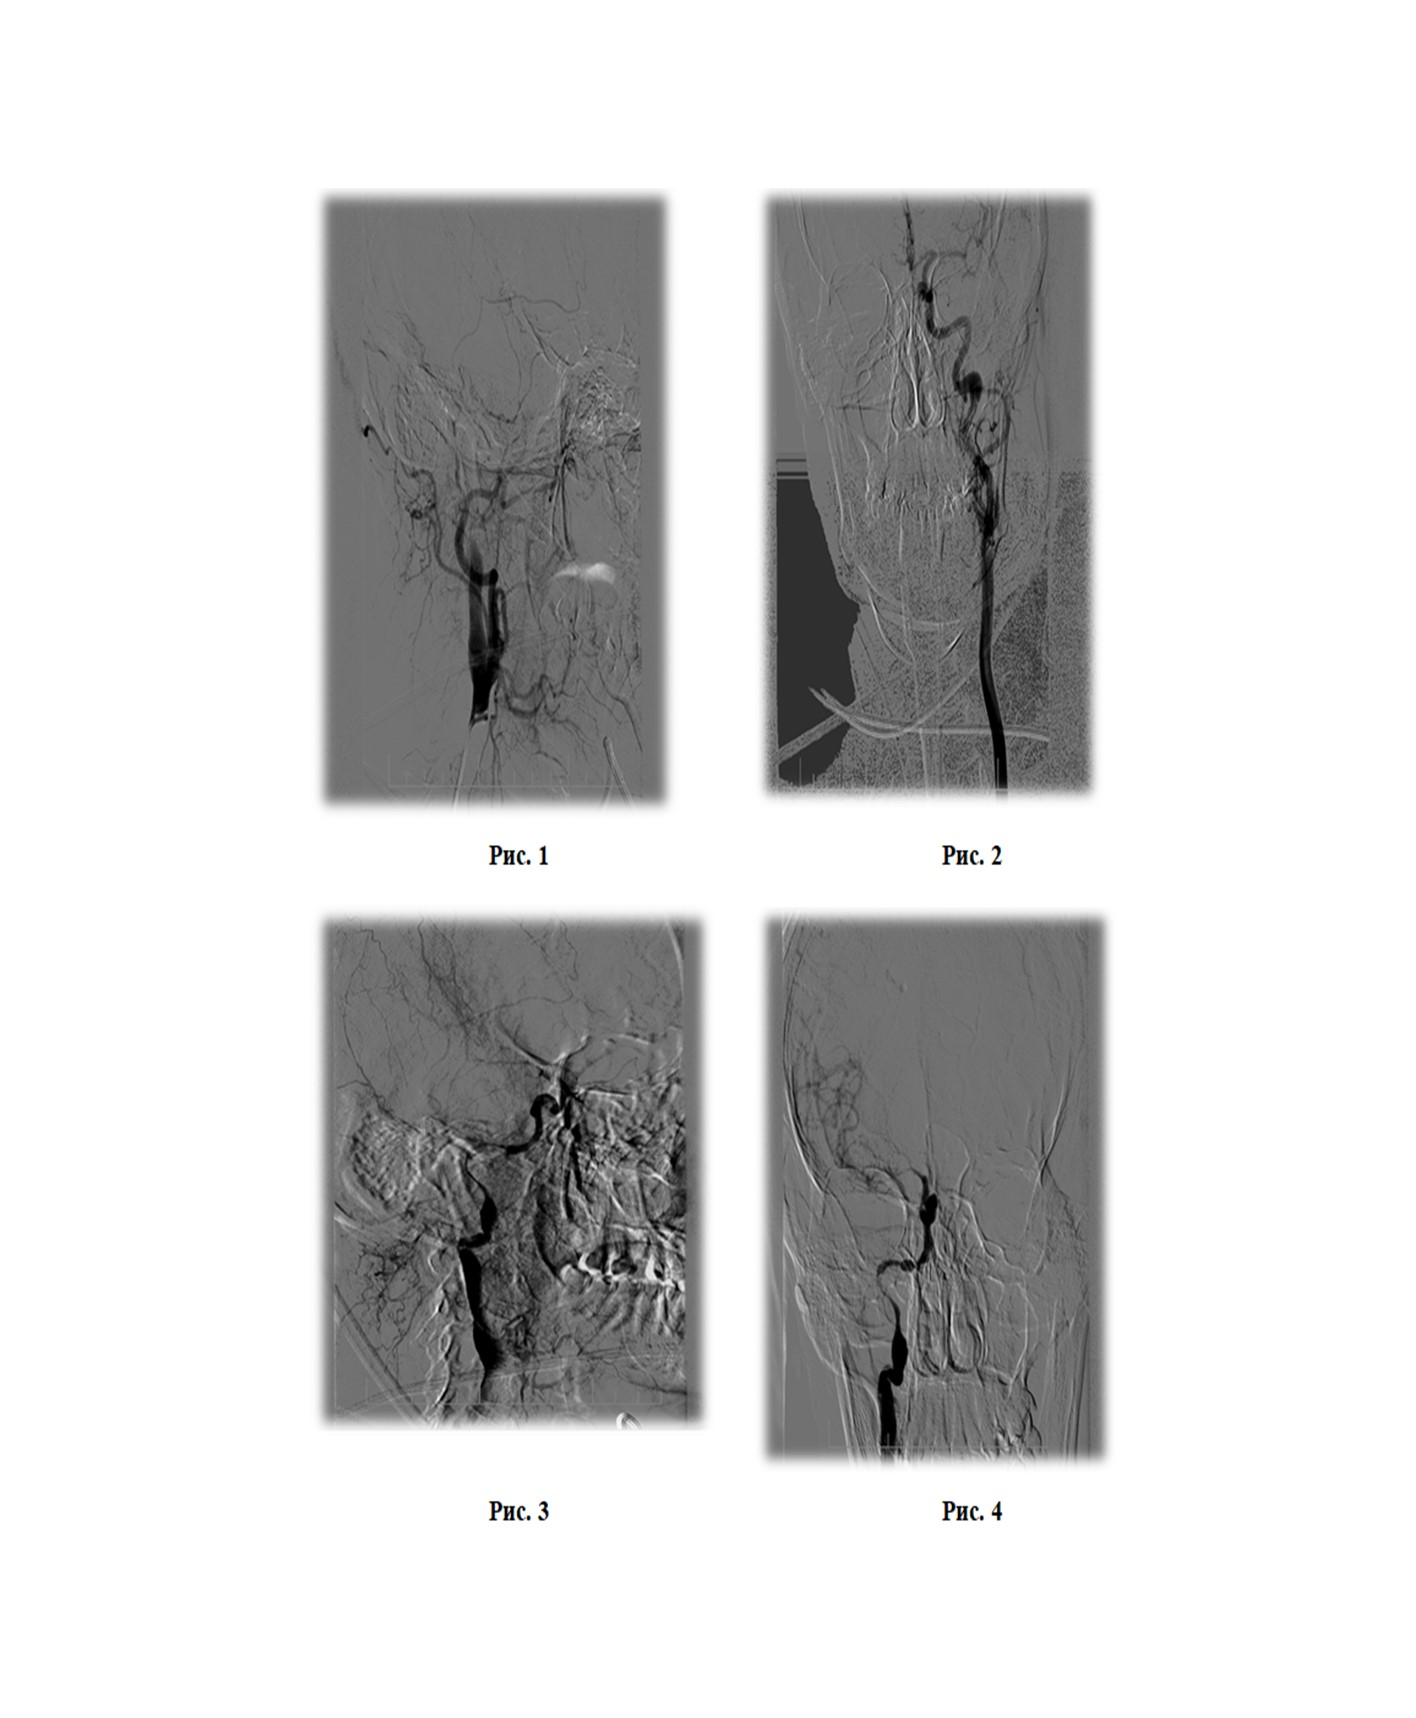

В 14:00 выполнена церебральная ангиография. Диагностирована окклюзия ПВСА в первом сегменте (симптом «пламени свечи»), в остальных артериях головного мозга - без видимых стенозов и окклюзий. Из левой ВСА через переднею соединительную артерию контрастируется правая передняя мозговая артерия (рис. 1, рис. 2). Учитывая молодой возраст пациентки и неотягощенный анамнез, а так же отсутствие поражений в других сосудистых бассейнах головного мозга была заподозрена спонтанная диссекция ПВСА. Коллегиально принято решение о выполнении механической тромбоэкстракции из ПВСА. Через проводниковый интродюссер 7F с применением проводникового катетера 6F с баллоном на конце для защиты от дистальной эмболии, выполнена реканализация ВСА до интракраниального отдела, дальше проводник завести не удалось. Выполнена тромбоэктракция стент-ретривером Solitaire FR с зоны сифона, получены фрагменты красного тромба. При последующем контрастировании ПВСА визуализирована до уровня сегмента C6, дистальнее оставалась окклюзирована. (рис. 3). Повторно проведена реканализация ВСА, микропроводник на микрокатетере заведен в правую среднюю мозговую артерию (ПСМА), после чего последовательно выполнены четыре тракции Solitaire FR из ПСМА с удалением множества красных тромбов максимальным размером до 5 мм. При контрольном контрастировании кровоток по ПВСА и ПСМА восстановлен, но имеется винтовая диссекция ВСА (симптом «четок») не доходящая до зоны интракраниального отдела (рис. 4, рис. 5). Диссекция лимитирует кровоток и стенозирует просвет артерии до 95%. При контрастировании через 5 минут признаки редукции кровотока. Для препятствия ретромбозу в ПВСА принято решение о стентировании артерии. Учитывая анатомические особенности, протяженность диссекции, а так же соответствие расходного материала принято решение о установке стента с доставкой под проводник диаметром 0,035", размером 6,0 х 150 мм. С техническими трудностями выполнена имплантация самораскрывающегося нитинолового стента от зоны сифона ПВСА до уровня средней трети правой общей сонной артерии (рис. 6, рис. 7, рис. 8). При контрольном контрастировании – раскрытие стента удовлетворительное, кровоток восстановлен и соответствует mTICI-3.